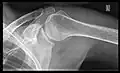

- Y-projection

The lateral contour of the shoulder should be positioned in front of the film in a way that the longitudinal axis of the scapula continues parallel to the path of the rays. This method reveals:[26]

- The horizontal centralization of the humerus head and socket

- The osseous margins of the coraco-acromial arch and hence the supraspinatus outlet canal

- The shape of the acromion

This projection has a low tolerance for errors and, accordingly, needs proper execution.[26] The Y-projection can be traced back to Wijnblath’s 1933 published cavitas-en-face projection.[27]

Transaxillary conventional radiography -

Y-projection conventional radiography